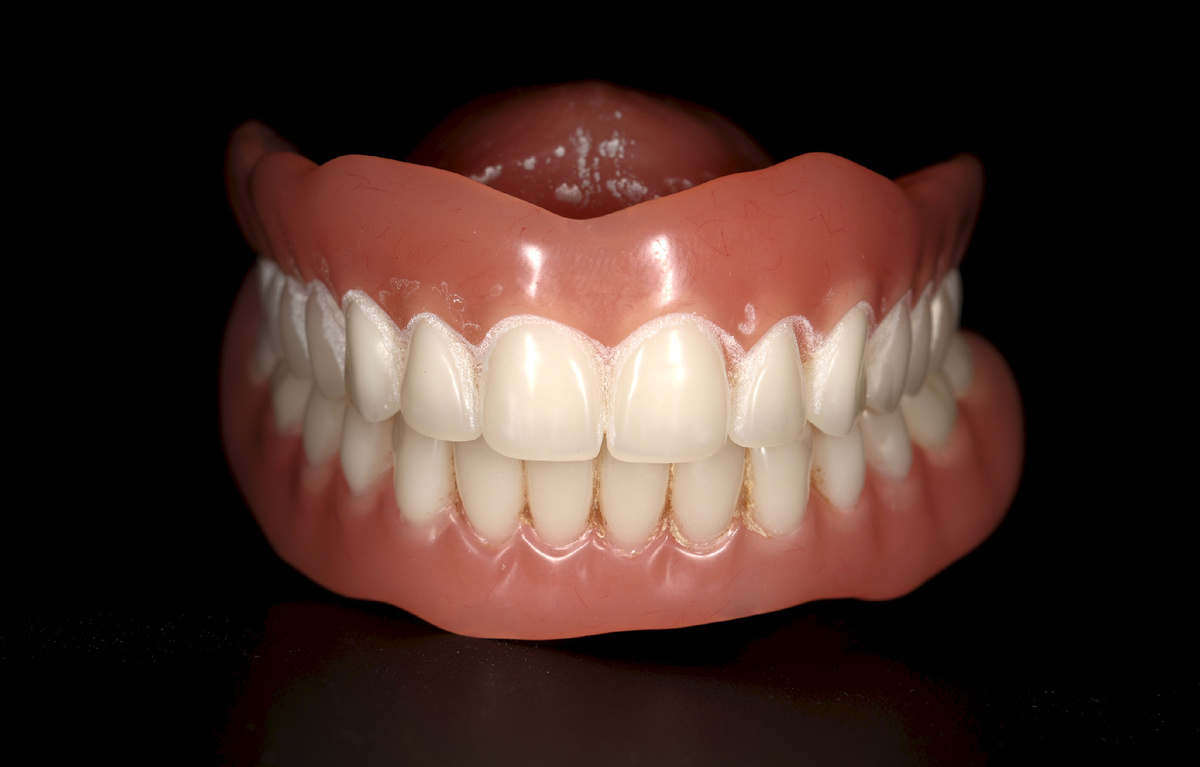

Поэтому, если человеку комфортно со съёмным протезом - это замечательно. Вот и нашей пациентке (+/- 70 лет человеку) тоже было комфортно жить с такими конструкциями на обеих челюстях:

Съёмные протезы, считаю, что симпатичные